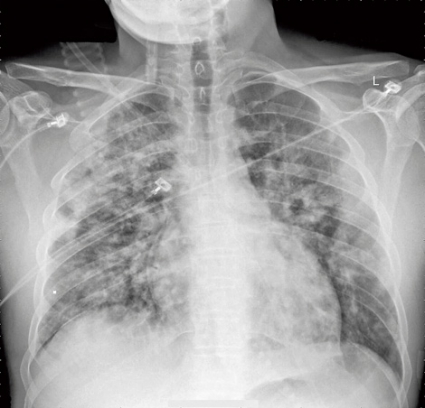

Blodtrycket var 120/75 mm Hg, pulsen 100 slag/minut och saturationen var 81 procent med oxygenmask med flöde 9 l/minut. Auskultation av lungorna avslöjade krepitationer bilateralt. Toraxröntgen på akutmottagningen visade infiltrat bilateralt, vilket tolkades som lungstas (Figur 1). EKG visade sinusrytm, i övrigt inga tecken på akut patologi. Akut ekokardiografi visade helt normala fynd och gav ingen misstanke om kardiellt betingat lungödem.

Konklusion: svår salicylatförgiftning komplicerad av icke-kardiogent lungödem.